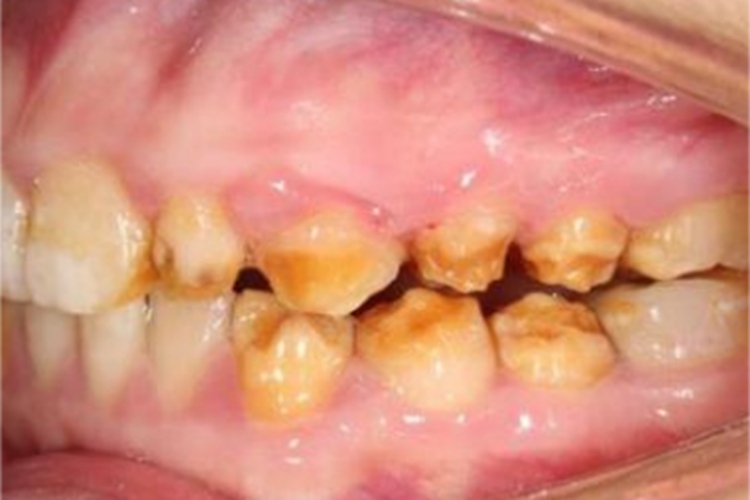

轻度牙釉质发育不全,通常牙冠形态完整,仅有色泽和透明度改变,可形成白垩色釉质,一般无自觉症状。重度牙釉质发育不全,牙面可出现带状或蜂窝状棕色凹陷。